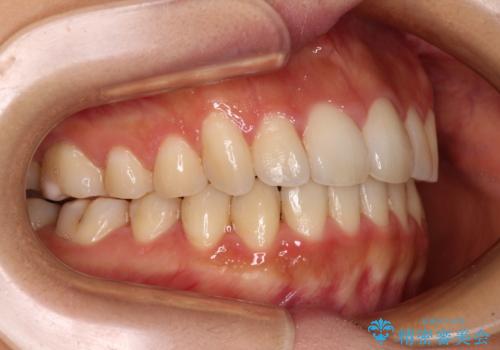

カリエールディスタライザーを併用した、咬み合わせ改善のインビザライン矯正

- 飛び出した前歯と口元の突出感を気にして来院された患者様です。

奥歯の咬み合わせを見ると、上顎が下顎に対して相対的に前方にありました。

口元の突出感を改善するためには、上顎臼歯を後方に移動させた咬み合わせにする必要があります。

インビザライン単体で改善することも可能ですが、達成する可能性が高くないため、カリエールディスタライザーという補助装置を併用して、より確実性を上げることとしました。

奥歯の咬み合わせを改善しながら、並行してインビザラインで歯列を整えることとしました。

カリエールディスタライザーを併用したことで、確実かつ短期間で治療を終えることができました。